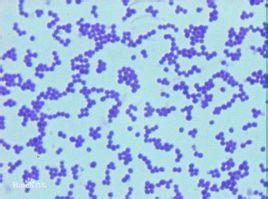

球菌是細菌中的一大類。對人類有致病性的病原性球菌(Pathogeniccoccus)主要引起化膿性炎症,所以稱為化膿性球菌(Pyogeniccoccus),其中革蘭氏陽性菌主要包括葡萄球菌、鏈球菌、肺炎球菌;革蘭氏陰性菌包括腦膜炎球菌和淋球菌等。